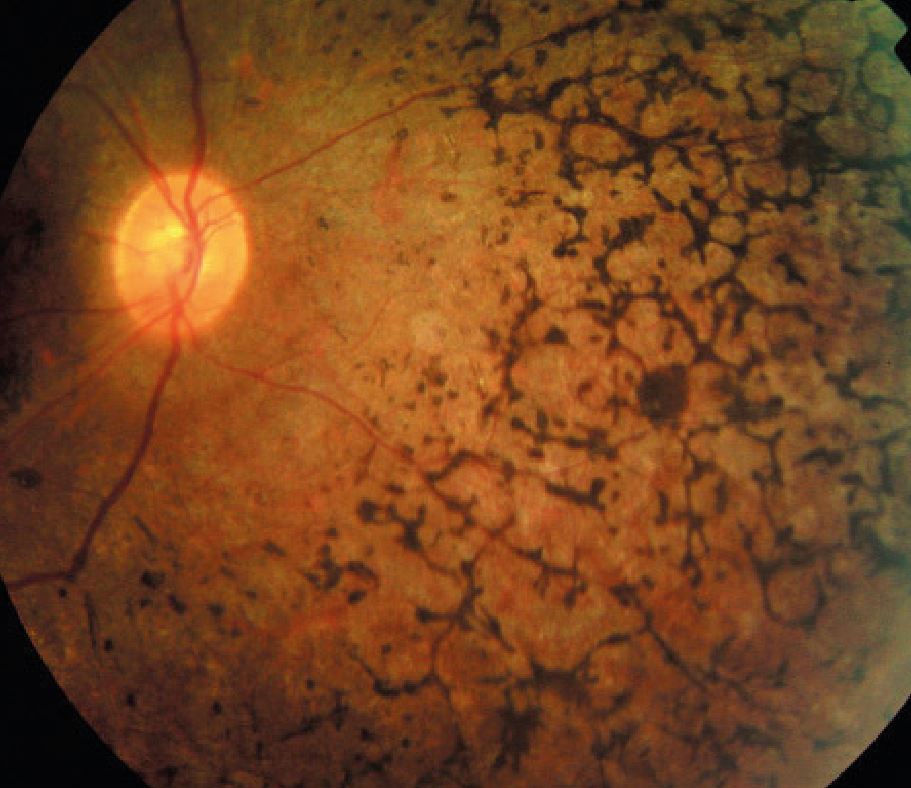

Атрофия зрительного нерва Лебера: Симптомы и лечение